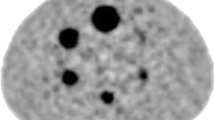

Endarterectomy and Histological Analysis

The histological quantification of inflammation was performed on H&E stained samples. The ocular micrometer was used to measure the total plaque area and area occupied by inflammatory cells in all the fields of view from all sections. The amount of inflammation per plaque was defined as the sum of all areas with inflammatory cells divided by the total area of all sections. A: ×200 magnification with inflammatory areas (marked by blue lines) containing mainly lymphocytes (i) and lipid macrophages (ii). B: ×400 magnification of areas with lipid macrophages